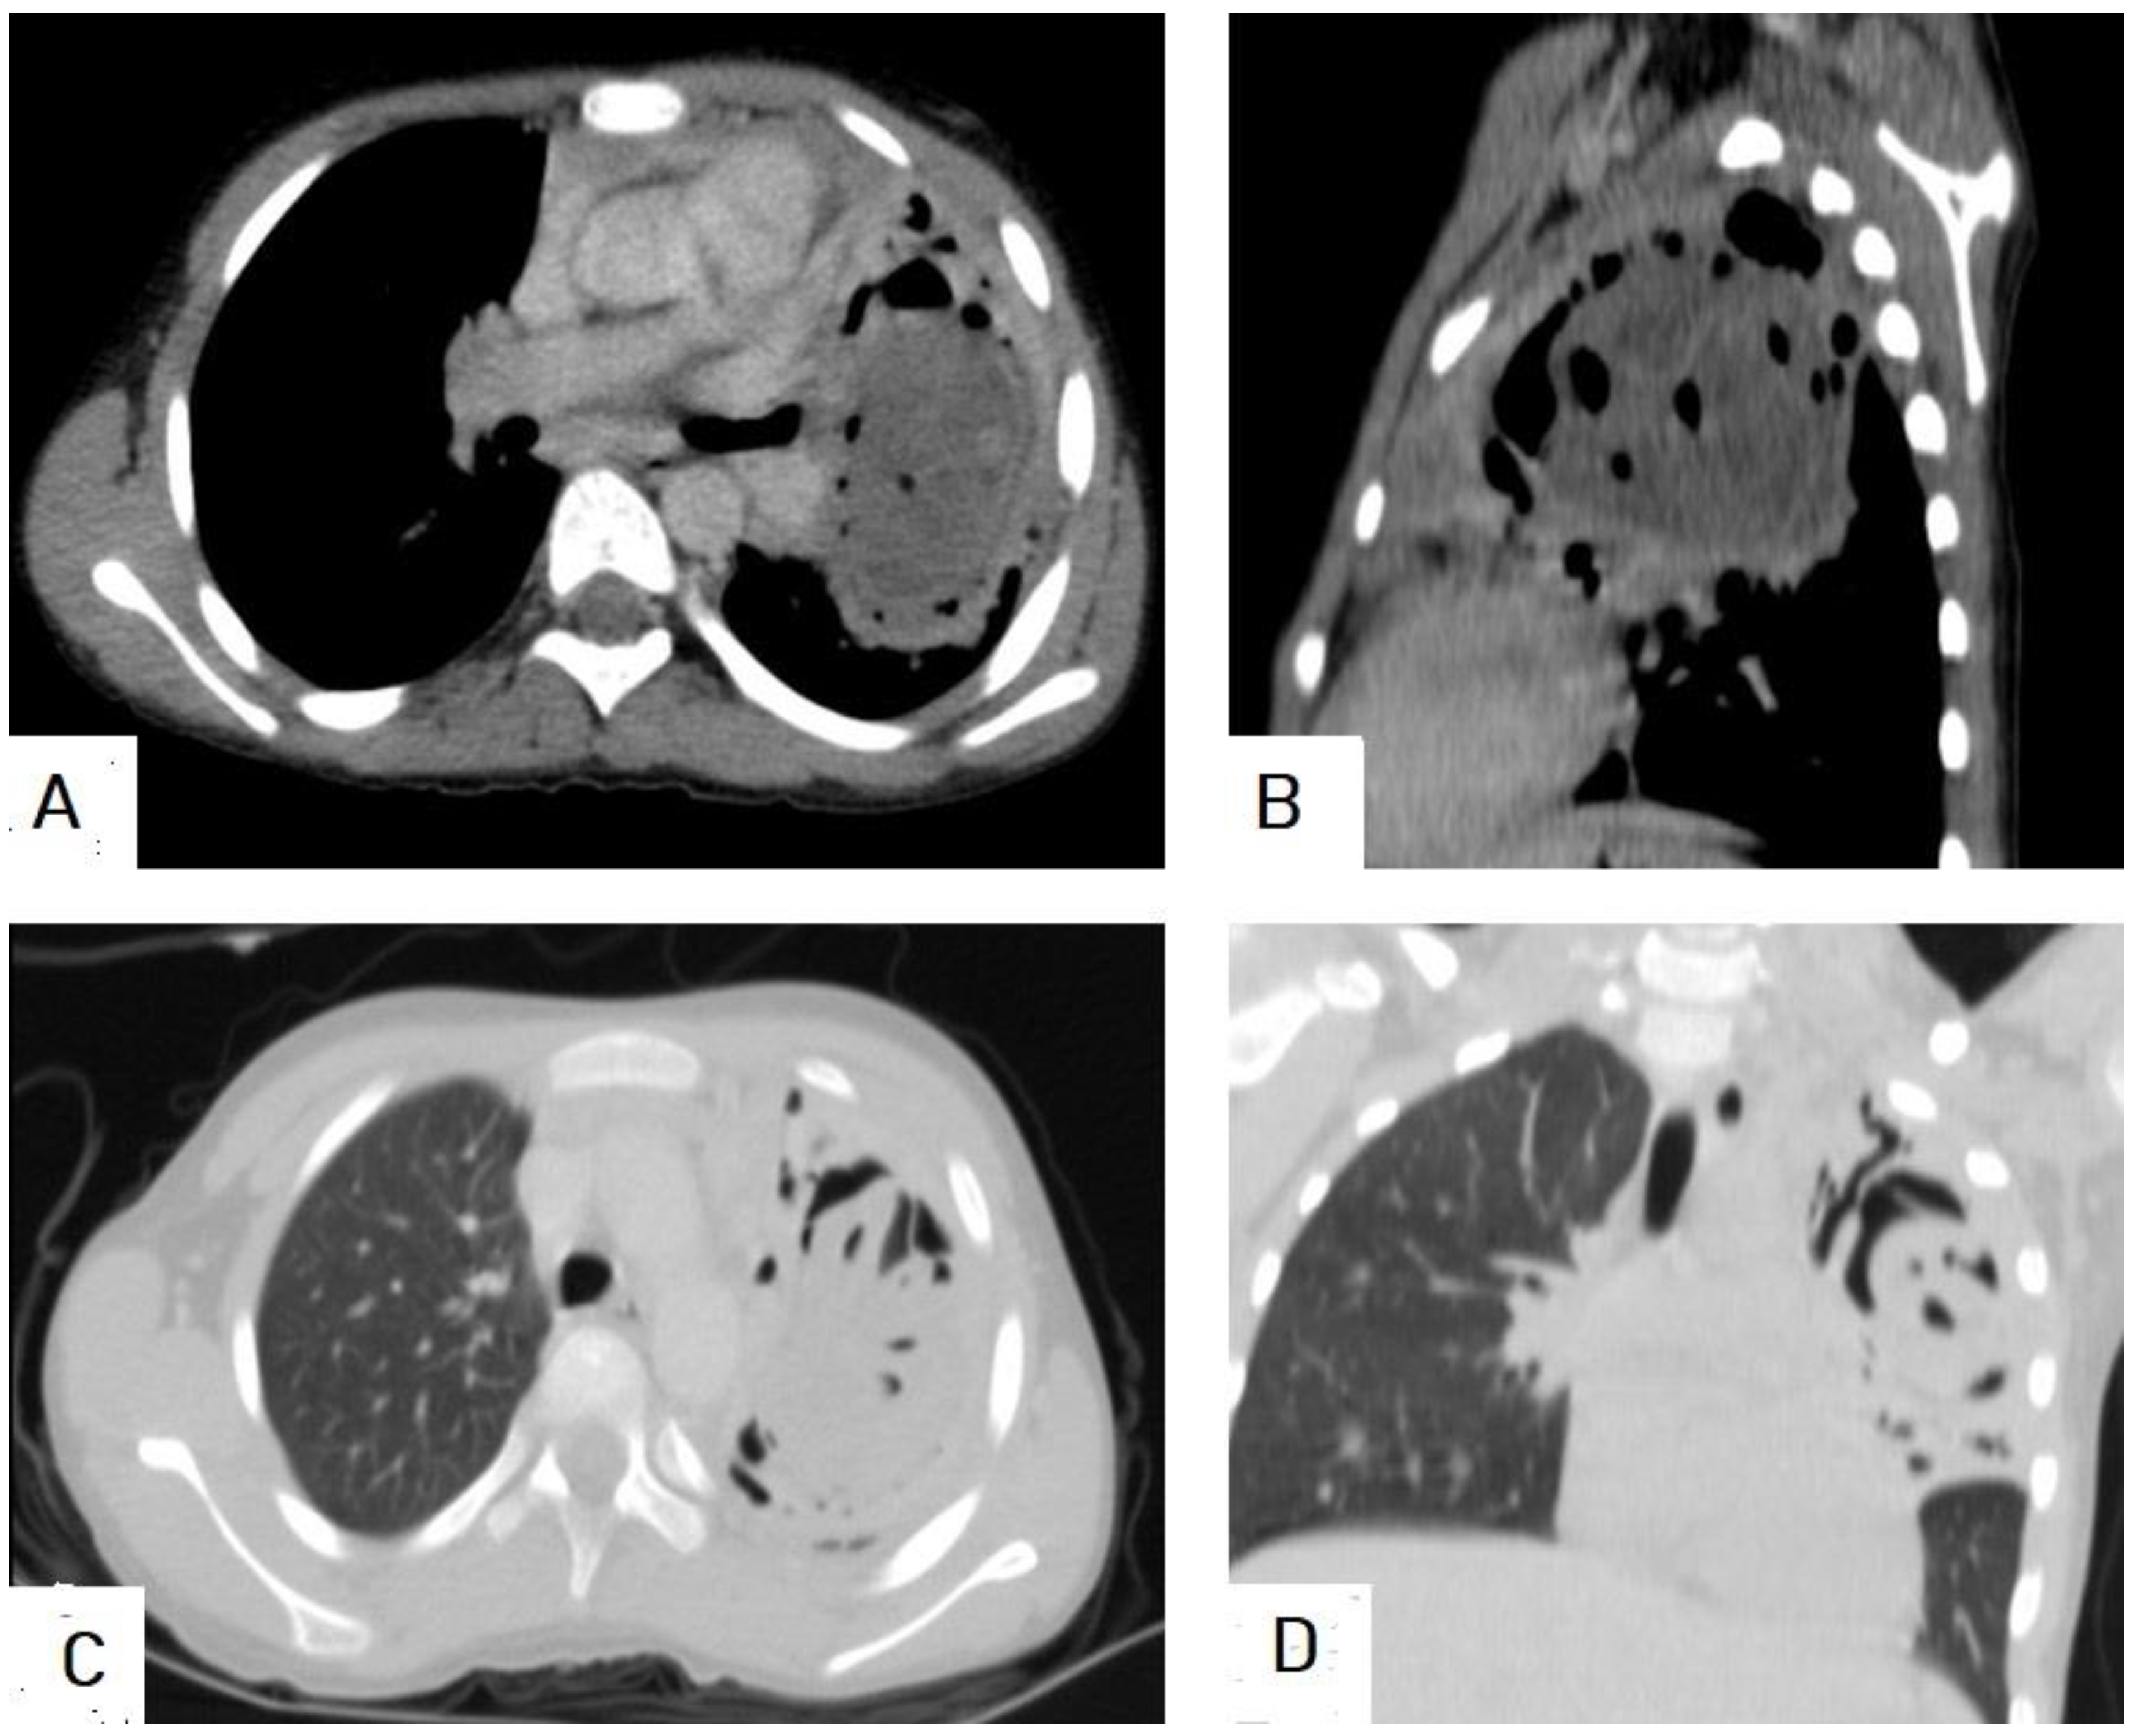

5.2. Hydatid Cysts of the Lung